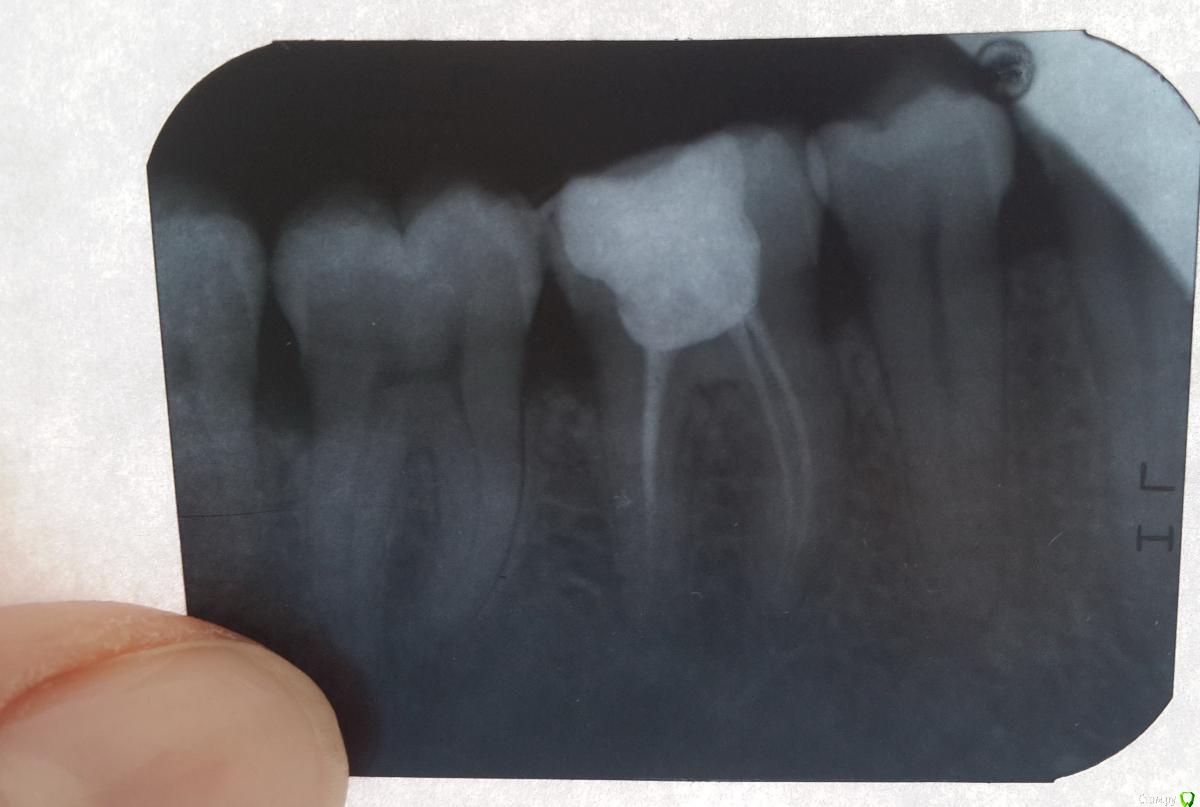

Le36 Опубликовано 21 мая, 2015 Поделиться Опубликовано 21 мая, 2015 Добрый день! Писала несколько дней назад про свой проблемный зуб (6-ка снизу), был глубокий кариес, первый раз нерв не удаляли, зуб болел в течении 1,5 месяца. В итоге три дня назад обратилась к стоматологу, было воспаление пульпы, нерв удалили, даже наркоз взял только со второго раза, чувствовалась боль. Вот сегодня третий день, зуб поднывает, меньше конечно чем до удаления нерва, но ноет, и как будто что то давит там где то далеко внутри него. Пломба стоит временная, завтра идти ставить постоянную. Подскажите, такая боль это нормально? И стоит ли торопиться ставить постоянную? Мне иногда кажется, что этот зуб уже никогда не пройдет (( На холодное и горячее не реагирует, единственно не приятно на него нажимать из-за временной пломбы. Врач у меня хороший, попасть к нему сложно, собственно и тянула ждала его возвращения из отпуска. Фото прилагается. Олеся. Ссылка на комментарий

red_butler Опубликовано 21 мая, 2015 Поделиться Опубликовано 21 мая, 2015 Я бы рекомендовал каналы переделать 2 Ссылка на комментарий

Le36 Опубликовано 21 мая, 2015 Автор Поделиться Опубликовано 21 мая, 2015 Я бы рекомендовал каналы переделатьСпасибо за ответ! По снимку вы советуете их переделать? А я думала в каналах тоже временная пломба стоит, которую он планирует завтра менять на постоянную. Ссылка на комментарий

red_butler Опубликовано 21 мая, 2015 Поделиться Опубликовано 21 мая, 2015 Спасибо за ответ! По снимку вы советуете их переделать? А я думала в каналах тоже временная пломба стоит, которую он планирует завтра менять на постоянную. Посмотрите во врачебном разделе, как выглядят правильно обработанные и обтурированные корневые каналы. Залог успешного эндодонтического лечения, полноценная механическая и медикаментозная обработка корневых каналов в условиях изоляции зуба коффердамом. Если в каналах временный материал, возможно доктор продолжит обработку в следующее посещение. 2 Ссылка на комментарий

Scrabble Опубликовано 21 мая, 2015 Поделиться Опубликовано 21 мая, 2015 (изменено) Наркоз действует только с первого раза, а вот местная анестезия на нижней челюсти с первого раза получается не у всех и не всегда. У хорошего врача с нормальной организацией времени в очереди никто не сидит. Что-то временное впихнуть при таком качестве механической обработки каналов не представляется возможным-там просто одиночные штифты конуса 02. Зуб нужно перелечивать. Удивляюсь нашим экономным людям, которые в Москве умудряются вот так полечить зубы. Изменено 21 мая, 2015 пользователем Scrabble 3 Ссылка на комментарий

Le36 Опубликовано 28 мая, 2015 Автор Поделиться Опубликовано 28 мая, 2015 Ну как, узнали?)Если вы мне сейчас скажите перелечивать зуб, я этого не переживу! Это уже четвертый раз будет!!! Ведь он же врач, заведущий, КМН, ну он же снимок видел, если бы что то ни так, переделал бы?! Ну не мог же он просто отмахнуться от меня, зная как я уже намучалась с этим зубом у другого врача, и денег не мало отдала. Что там ни так в этих каналах, скажите мне?! Ссылка на комментарий

Le36 Опубликовано 28 мая, 2015 Автор Поделиться Опубликовано 28 мая, 2015 Наркоз действует только с первого раза, а вот местная анестезия на нижней челюсти с первого раза получается не у всех и не всегда. У хорошего врача с нормальной организацией времени в очереди никто не сидит. Что-то временное впихнуть при таком качестве механической обработки каналов не представляется возможным-там просто одиночные штифты конуса 02. Зуб нужно перелечивать. Удивляюсь нашим экономным людям, которые в Москве умудряются вот так полечить зубы.Перелечивать нужно каналы? Ссылка на комментарий